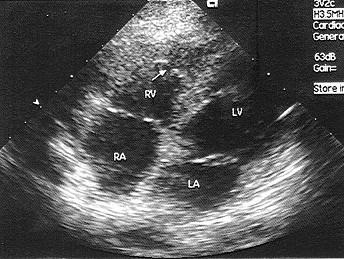

该病例最可能的诊断?(?)A.右室流出道狭窄B.肺动脉瓣狭窄C.室间隔缺损D.右室双腔心E.以上都不是

问题 该病例最可能的诊断?(?)

选项 A.右室流出道狭窄 B.肺动脉瓣狭窄 C.室间隔缺损 D.右室双腔心 E.以上都不是

答案 D